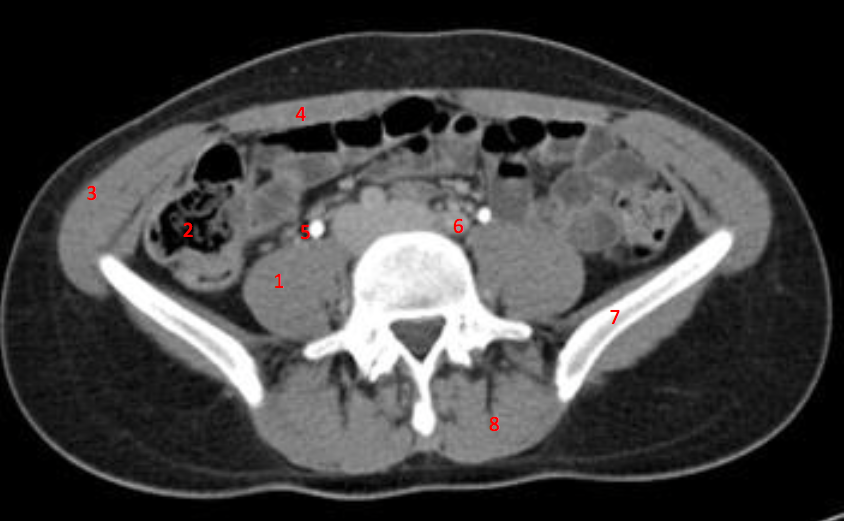

Number 3?

IVC

Number 1?

R Kidney

Number 2?

Number 4?

Rectus abdominus

Number 7?

Bowel (probably large)

Number 5?

Rt ureter

Number 8?

Bladder